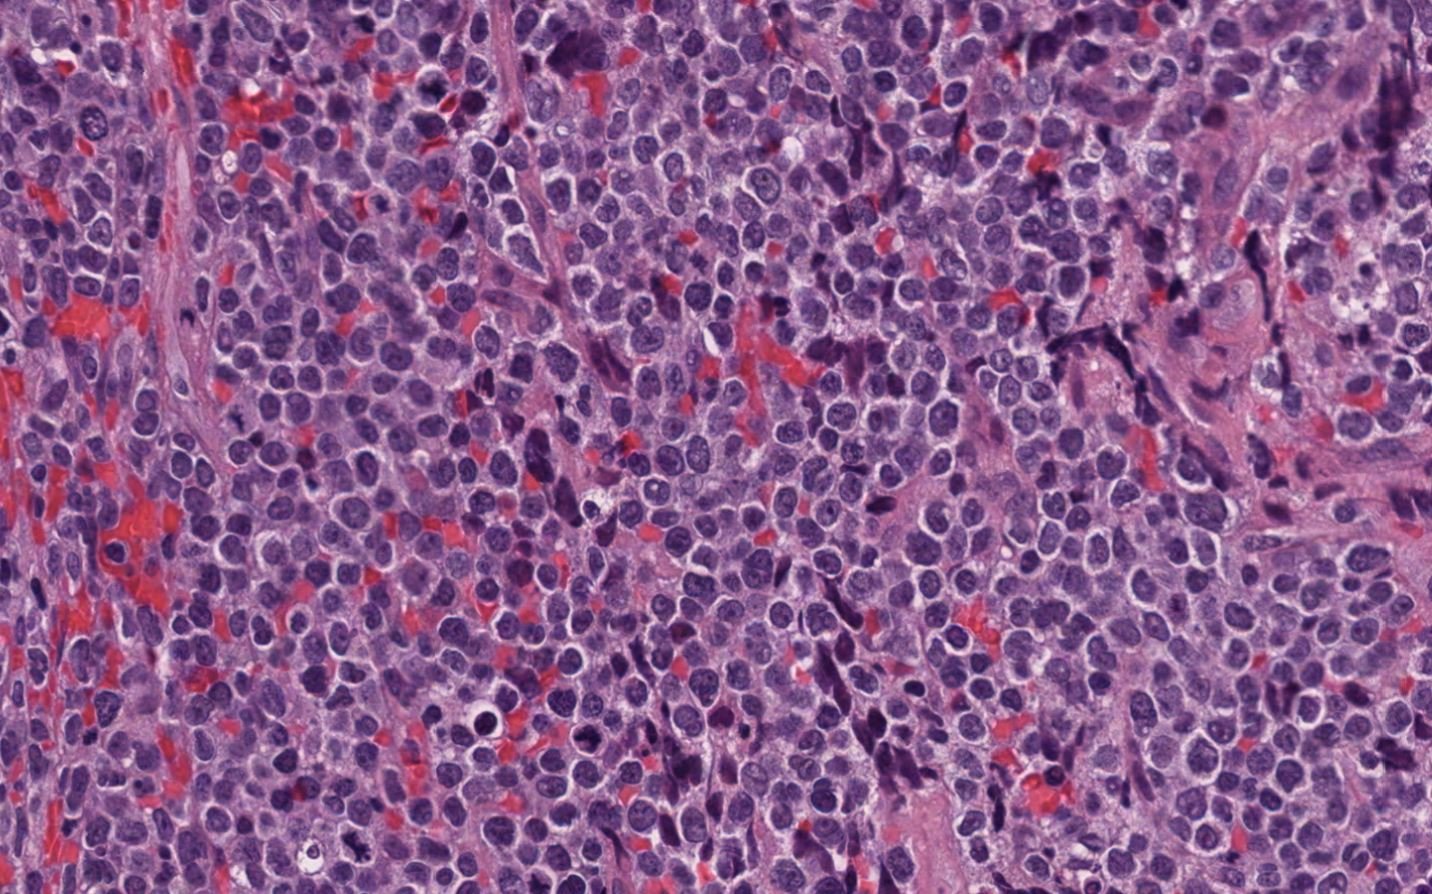

Case: MaxillaryMass

Specials to Order:

Final Diagnosis: